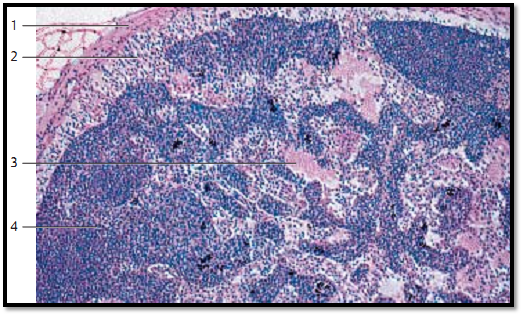

Lymph nodes, nodi lymphatici , are oval or bean-shaped organs. They function as biological filters in the lymphatic circulation. Their sizes may range b e-tween several millimeters to more than 2 centimeters. They are encapsulate d by connective tissue collagen fibers 1 . Connective tissue divisions from the capsule, the trabeculae, extend into the interior node. Sporadic myocytes are found inside the capsule. Trabeculae form the basic skeleton of the organ. The finer network of reticulum cells and the argyrophilic fibers (reticular fibers) is interspersed with this skeleton. The web contains considerable numbers of lymphocytes and macrophages (lymphoreticular organ ). Lymph nodes consist of the cortex 2 and inner medulla 3 . Blood vessels enter at the hilus region, and efferent lymph vessels (vasa efferentia) from the lymph node exit at the hilus. Several afferent lymph vessels (vasa afferentia) pierce the capsule and bring lymph into the lymph node. The figure very clearly shows the heavily stained cortex and the lighter medulla. In the cortex, we see a large number of nodular follicles with germinal centers ( lymphatic nodules). Please, note the central medullary sinus 4. Human inguinal lymphatic node.

1 Capsule

2 Corte x with secondary follicles (lymphatic nodules)

3 Medulla

4 Medullary sinus

Stain: alum hematoxylin-eosin; magnification: × 20